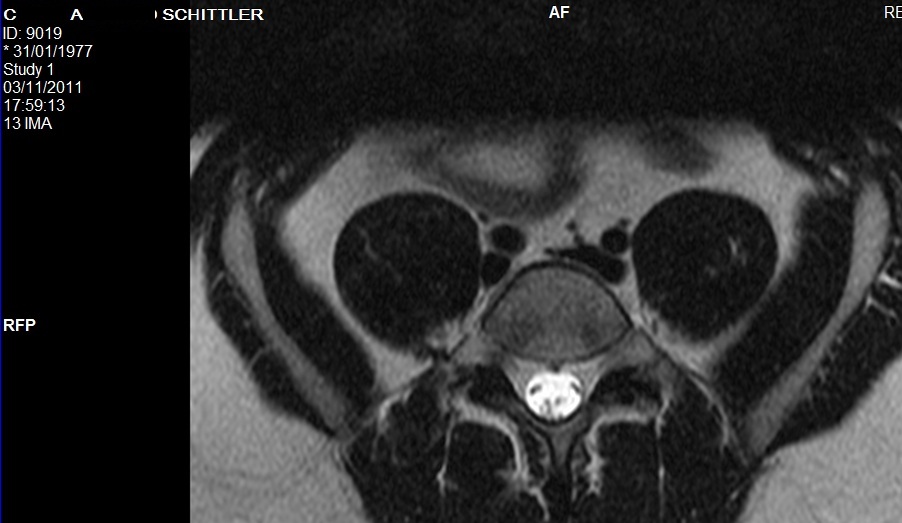

Foi solicitada uma RNM lombar, a qual foi detectada uma volumosa hérnia discal extrusa no segmento L4-L5 e protusão discal no segmento L5-S1.

Com 6 meses foi solititada uma nova RNM onde observou diminuição considerável da hérnia do segmento L4-L5 e da protusão do segmento L5-S1 (apenas abaulamentos).

Imagens da 1º RNM, realizada no dia01/06/2011:

Imagens da 2 RNM, realizada no dia 03/11/0211: